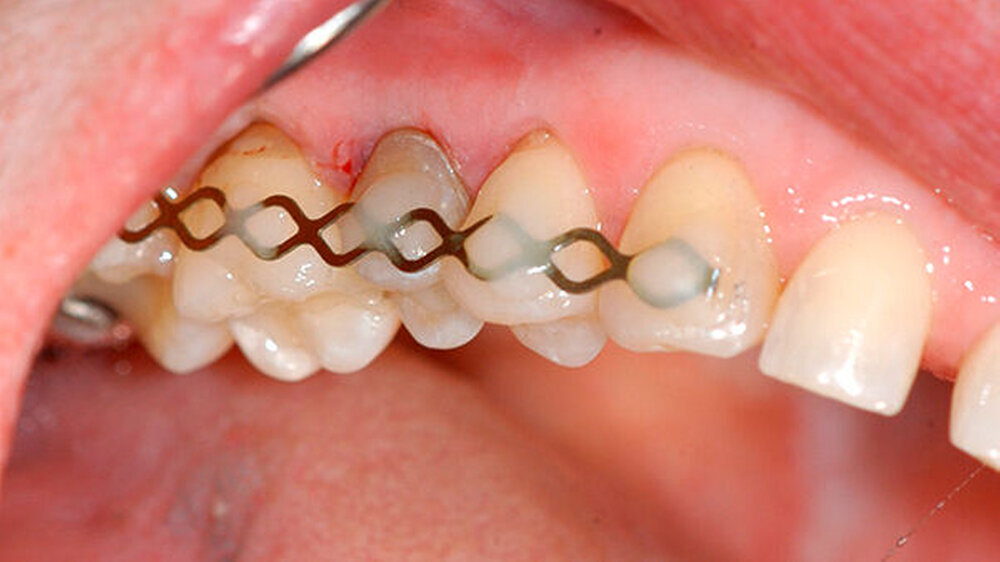

Nachdem die Patientin darüber aufgeklärt wurde, wie der Zahn möglicherweise erhalten werden kann, wurden die Zahnfragmente nach Gabe einer Infiltrationsanästhesie schonend extrahiert (Abbildung 3). Nach der Extraktion wurden die zwei Zahnfragmente zunächst in der Zellnährlösung einer Zahnrettungsbox (Medice Pharma, Iserlohn) geschwenkt, um sie von Blut und Gewebe zu säubern. Das apikale Granulationsgewebe, das bei der Extraktion an der Wurzelspitze verblieben war, konnte manuell mit einer Luer Zange entfernt werden.